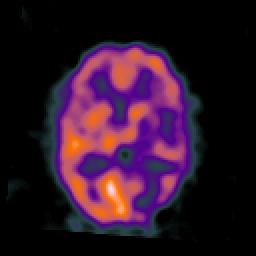

SPECT TC Study #3 -- Slice #30

[Home][Help][Clinical][Tour 1][Tour 2][Tour 3] Slice 30